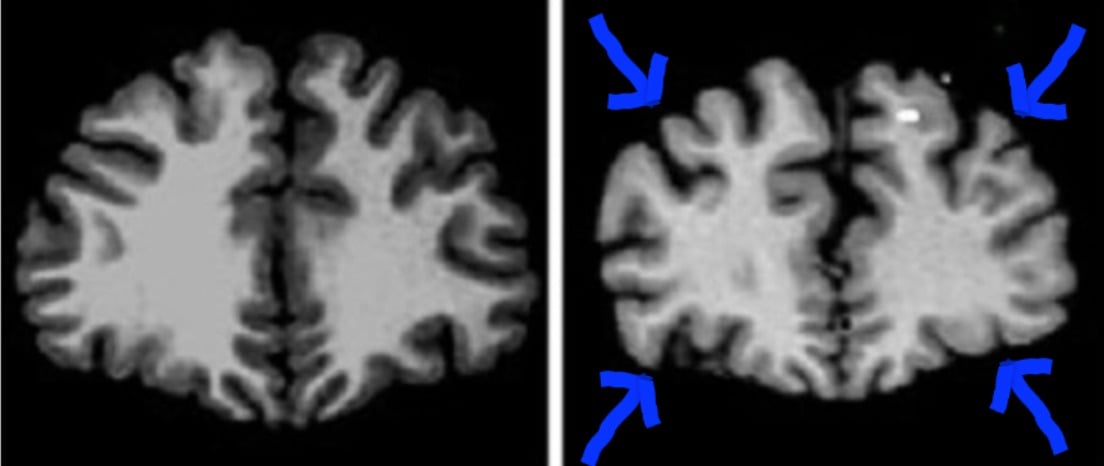

Vous le savez peut-être, en vieillissant le cerveau rétrécit.

Il se « tasse ».

Comme sur la photo :

A gauche, le cerveau en pleine santé d’un jeune homme de 24 ans.

A droite, le cerveau d’un homme de 79 ans.

On voit bien que la taille du cerveau a diminué.

Car des scientifiques de l’Université de Dakota du Sud aux États-Unis ont découvert un lien étroit entre la présence de ce fluide dans le sang et la taille du cerveau.

En étudiant un groupe de 1000 femmes de plus de 65 ans, ils ont démontré qu’on pouvait agir sur le volume du cerveau, et limiter le vieillissement cérébral.

Simplement en augmentant les niveaux d’or liquide dans le sang.